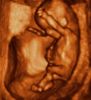

» Život před narozením

12. týden